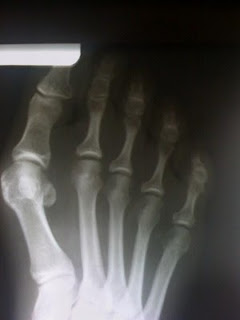

Haglund's deformity, sometimes called the "pump bump," occurs when back straps of heels dig into the tissue around the Achilles tendon. Too-tight shoes can bring on bunions, an enlargement of bone or tissue at the base of the big toe that pushes the big toe toward the second toe.

Pointy shoes can worsen hammertoe by forcing the toes to bend at the middle joints, eventually causing them to stay bent and rigid even when barefoot.